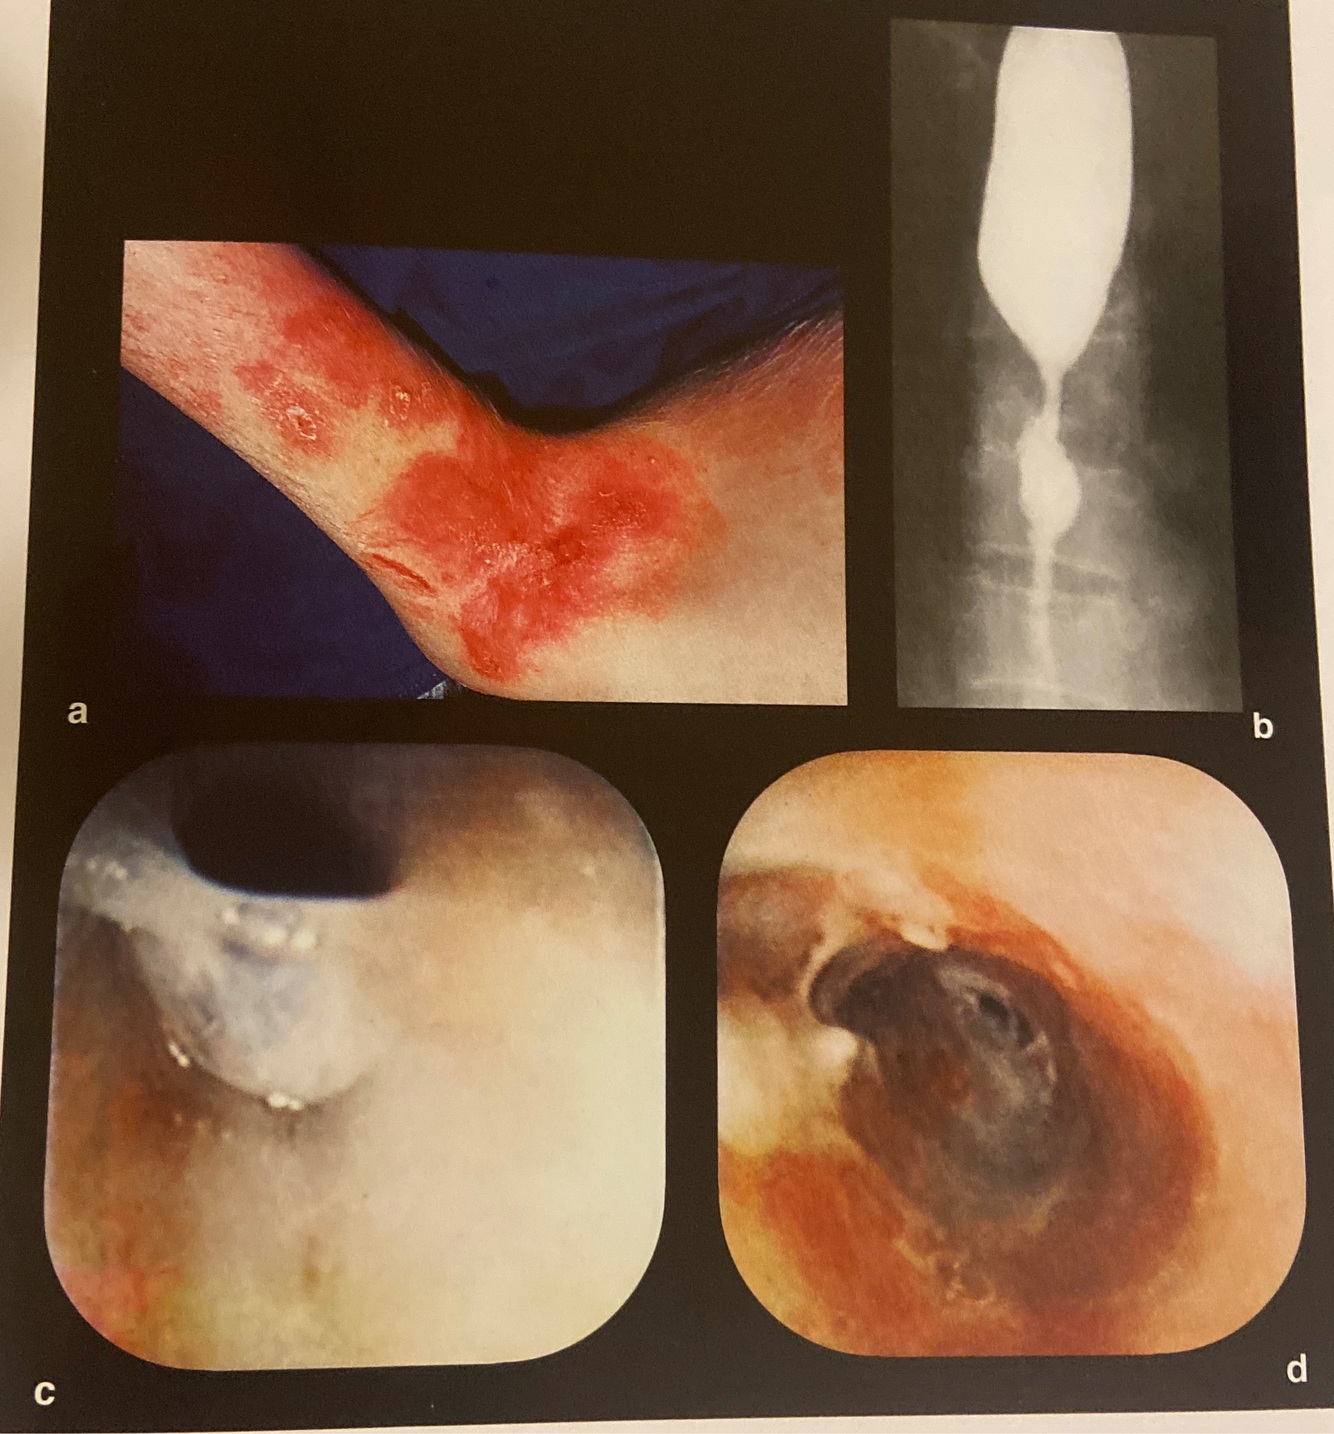

18

a e b Endoscopia de fenda (cleft

laringotraqueoesofágica (grau II)